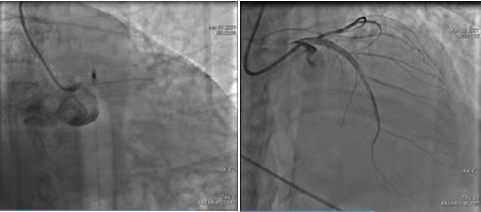

術(shù)前CAG示:左主干閉塞 IABP支持下開通閉塞血管